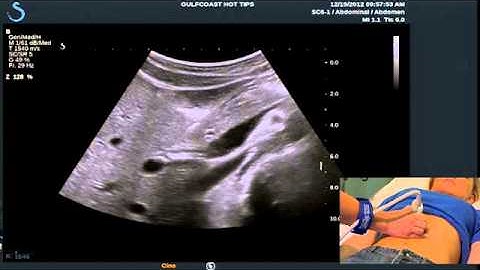

How to Get Great Pulsed Wave Doppler from the Main Portal Vein